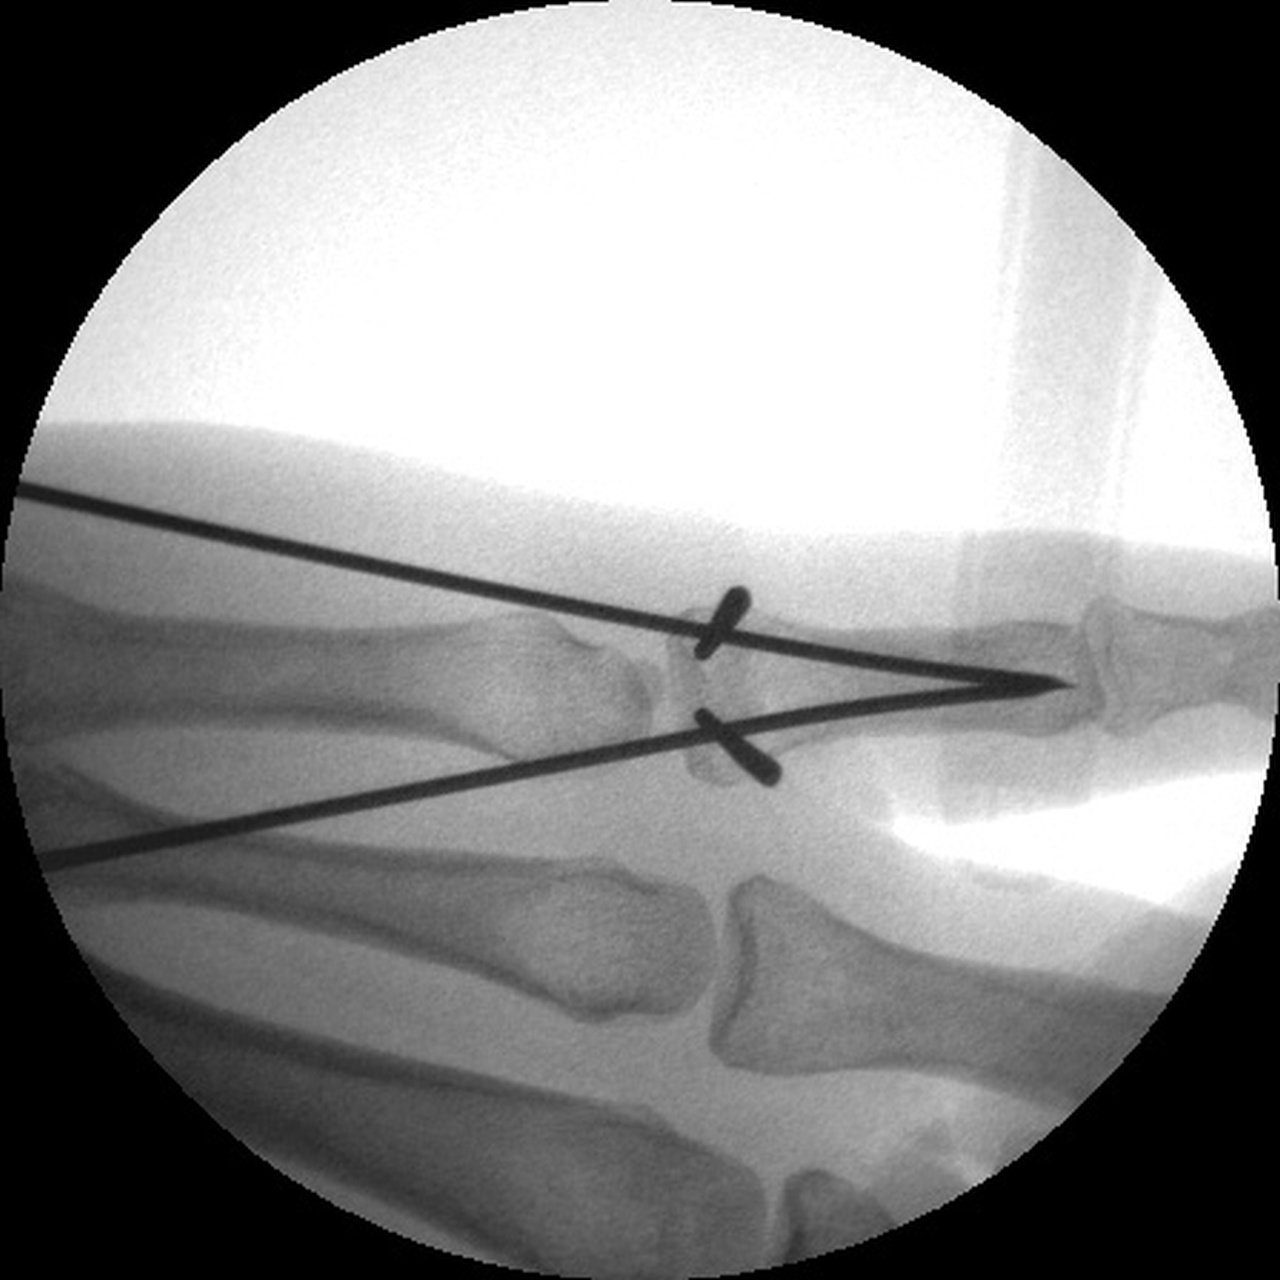

| Manipulation and closed reduction: |

| Percutaneous pins placed across the fracture line and also dorsal to palmar into the proximal fracture fragment. |